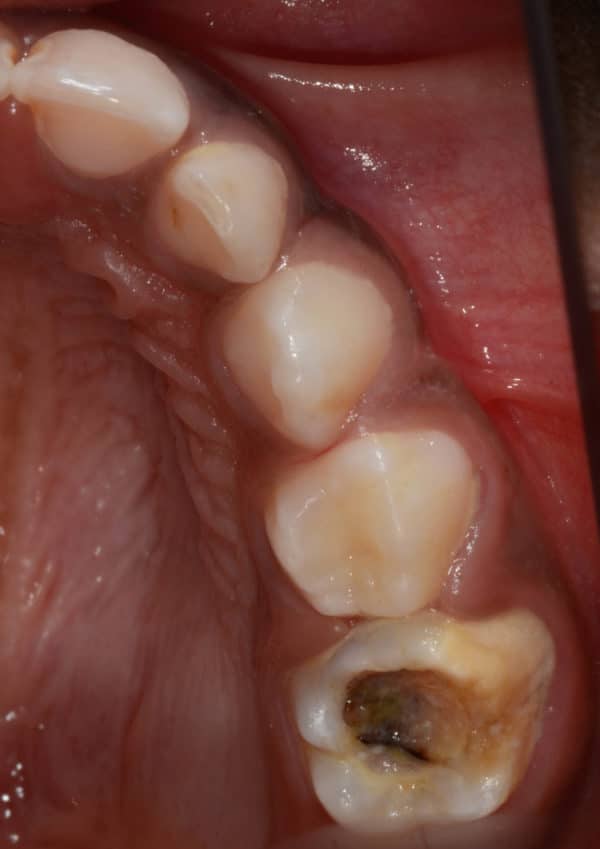

Caries dentaires affectant deux molaires de lait

Caries dentaires affectant deux molaires de lait. Elles peuvent être cachées entre les dents, non détectables lors de l’examen de dépistage. Une petite radiographie intra-orale révélera l’existence de ces caries et évitera leurs progression souvent assez rapide.